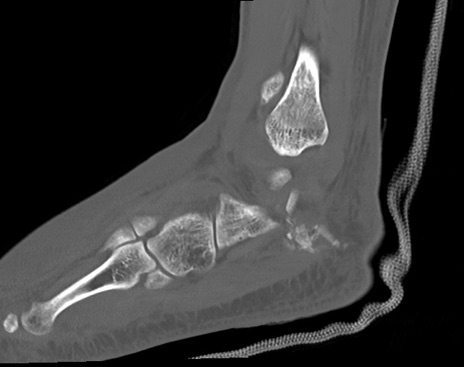

症例37 左足関節CT(矢状断像)

左足関節CT